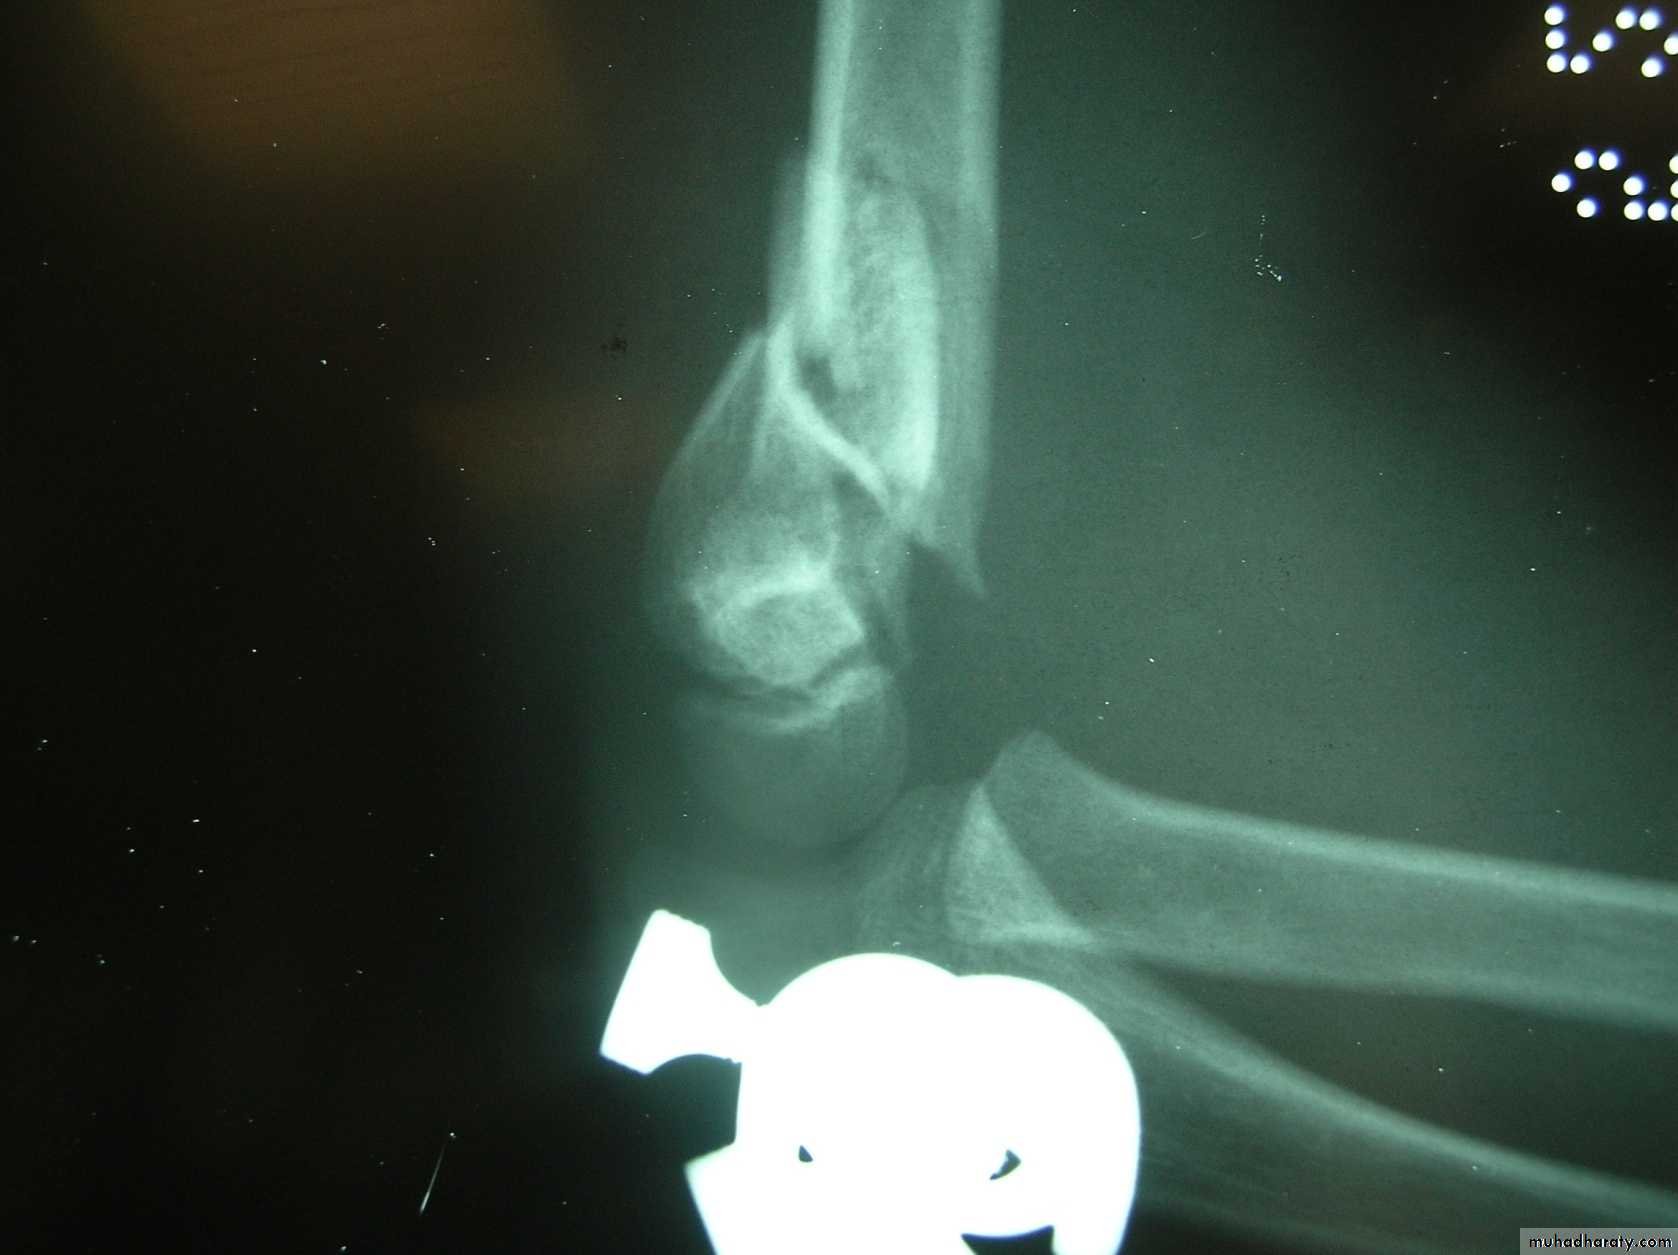

This classical Type III pattern

is obviously a flexion injury.With these one needs to be

prepared to do an open reduction !!

not flexed,but also it is not extended to any degree.

This also is a Type III Flexion Pattern.

What is differentabout this fracture?

But, if not recognized as such, it may be a problem.

This fracture was irreducible,

and required an open reduction !!!

There are some clues to these occult flexion injuries.

1. The distal fragment is not extended,

however,it may not be flexed to any degree.

It may be

rotated!!2. The distal fragment is in valgus.

3. The medial spike of the proximal fragment is usually posterior.

4. There may be clinical signs of ulnar nerve dysfunction.

Why are these fractures irreducible ?

The location of the proximal medial spike is critical.The medial spike

is pressing againstthe ulnar nerve.

It is also posterior to the

intermuscular septum.

What is the operative approach ?

It involves an anteromedial incision.